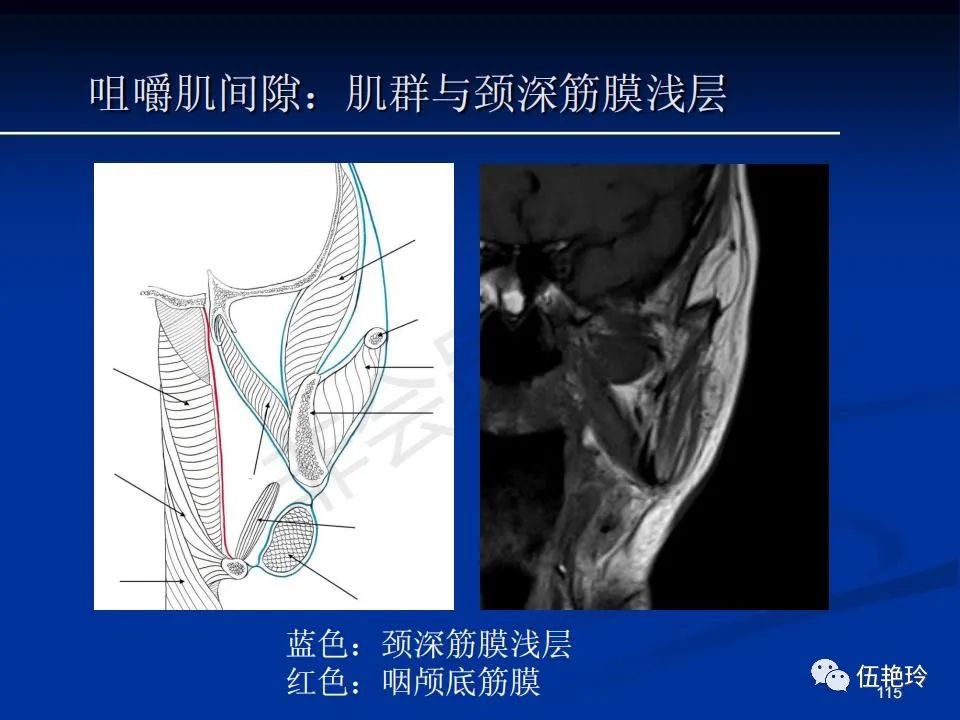

颞下窝与咀嚼肌间隙